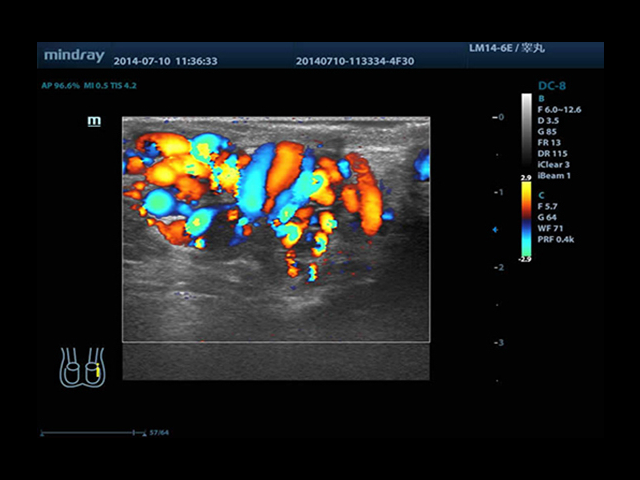

Mindray DC-8 Exp оснащен новым поколением датчиков с увеличенным количеством элементов и инновационной технологией "3T". Это позволяет достичь высокой детализации и качества изображения. Благодаря новейшей технологии iFlow, можно визуализировать даже самые мелкие сосуды и кровеносные пути.

Сверхширокополосная нелинейная обработка изображений снижает визуальные шумы на 30% по сравнению с другими системами. Технология iClear позволяет устранить зернистость изображения, а iBeam (технология пространственного компаундинга) обеспечивает высокое качество сканирования органов и тканей под различными углами.